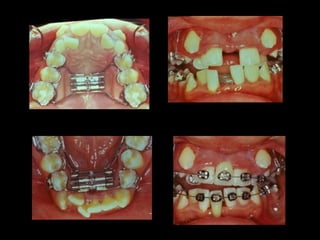

La paciente fue manejada iatrogénicamente por 5 años

Utilizando diferentes implementos ortodóncicos

La regla es clara: Laterognatias de más de 2º son quirúrgicas

La paciente muestra una franca disgnatia, clínicamente

observamos malposición dentaria secundaria a la falta de

armonía máxilomandibular.

Marcada Clase III

Hábito Lingual

Sobremordida horizontal: –1.5 mm

Sobremordida vertical: + 1 mm.